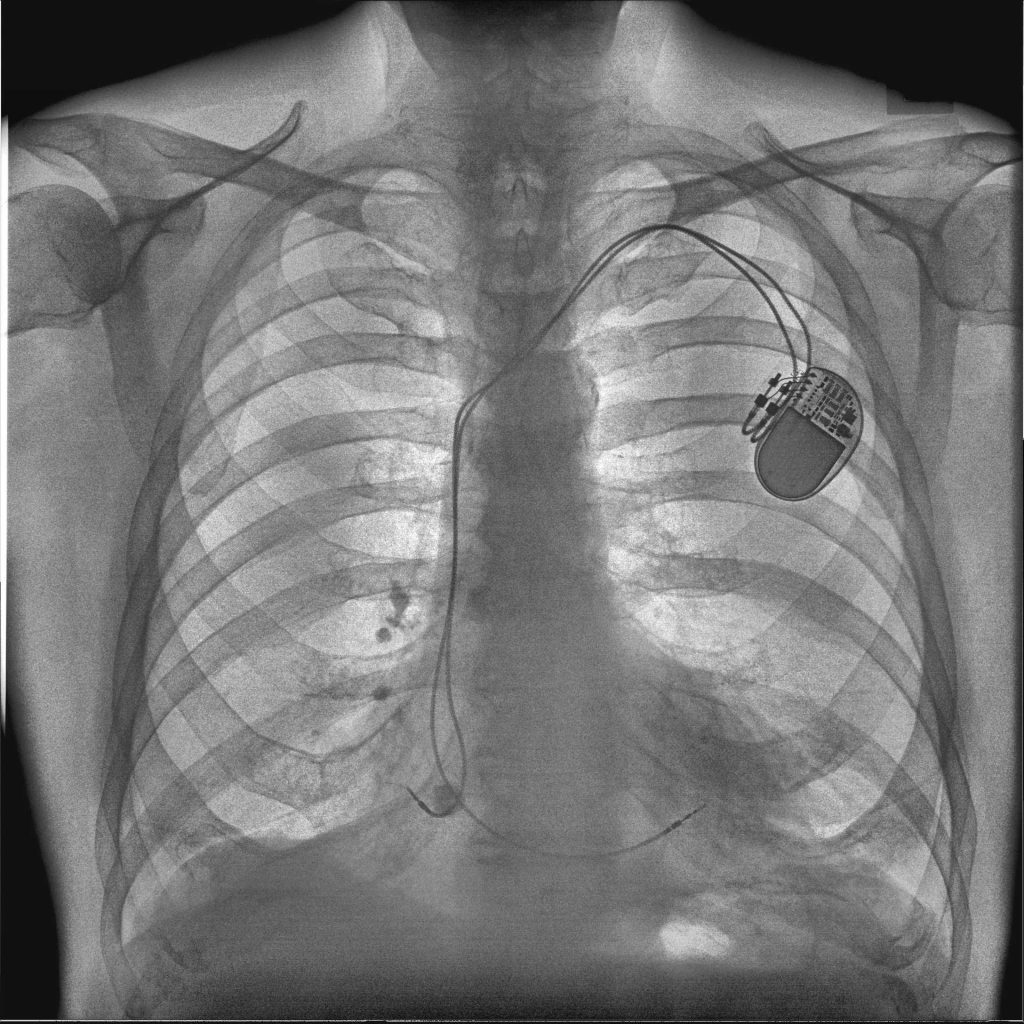

Reveal 35C has a triple layer design which simultaneously captures three images in a single exposure, all without motion artifacts. To do this, the Reveal 35C only requires the standard radiation dose. The dosage does not need to be increased to achieve dual-energy imaging.

Of the three images is a traditional DR image which captures both bone and soft tissue, as well as supplemental bone and soft tissue images. This enables easy material differentiation for radiologists.

On the left is the traditional DR image, in the middle is the soft tissue image, and on the right is the bone image.